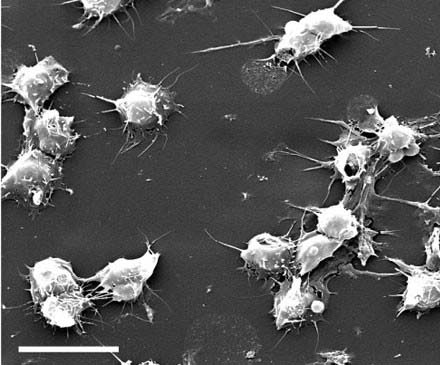

سلولهای بنیادی مغز استخوان انسان